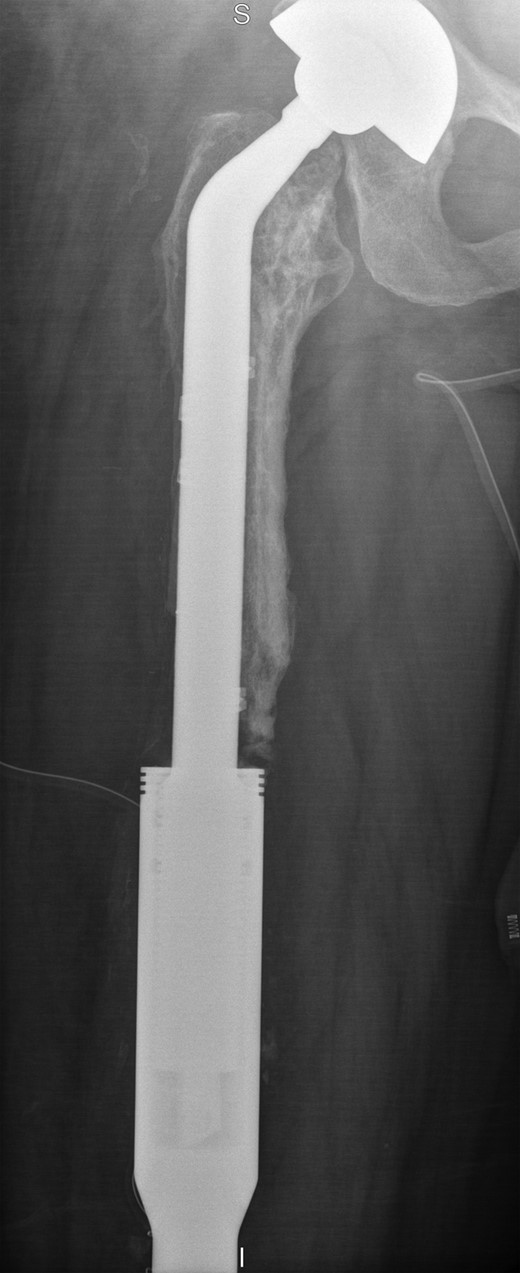

The operation was carried out by the senior author and the customized distal femoral prosthesis was successfully cemented over the pre-existing internal proximal femoral replacement (Figs 6 and 7).

Retained proximal femoral component with new custom-made cement-linked distal femoral prosthesis visible in lower half of the image.

New custom-made distal femoral prosthesis cement-linked to original salvage proximal femoral component visible in upper half of the image.